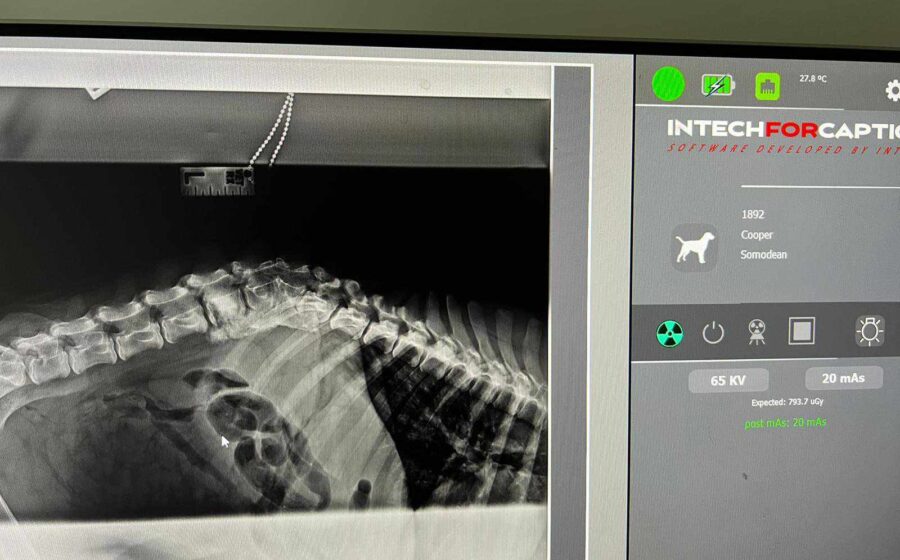

Sommersprosse stand seit seiner Geburt wacklig auf seinen Hinterbeinen. Sein 92-jähriger Besitzer, der Sommersprosse ausschließlich im Haus hielt, weigerte sich jedoch, den Welpen untersuchen zu lassen. Um die Wachstumsentwicklung von Sommersprosse zu unterstützen, ging unsere Tierschützerin Tina regelmäßig vorbei und brachte Futter, Vitamine, Mineralien und Ergänzungsmittel mit. Eines Tages beschloss der alte Mann, Sommersprosse nach draußen zu lassen, wo er prompt von einem Auto angefahren wurde. Daraufhin hat Tina Sommersprosse zu sich in Pflege genommen und ihn direkt untersuchen lassen. Auf den Röntgenbildern wurden angeborene Schäden der Wirbelsäule und Hinterläufe, sowie ein weiterer Wirbelsäulenschaden durch den Unfall festgestellt. Spazierte Sommersprosse anfangs noch auf wackligen Hinterbeinen durchs Leben, hat sich seine Gehbehinderung jetzt deutlich verschlechtert. Auch ist der süße Bub hierdurch größtenteils inkontinent geworden und braucht spezielle Versorgung.

Das bedeutet, dass seine Blase manuell entleert werden muss.